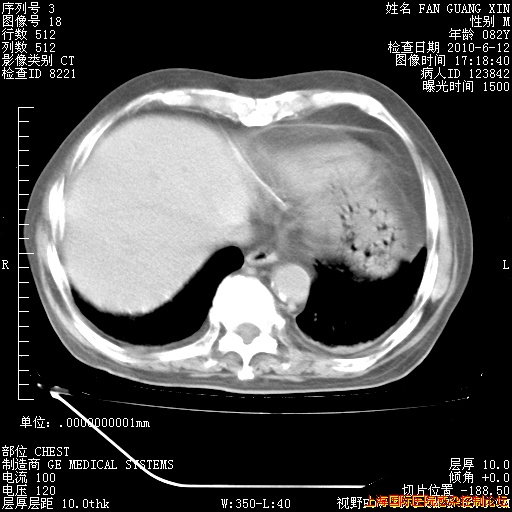

补发6月12日肺部CT肺窗

6月12日肺窗

6月12日纵膈窗